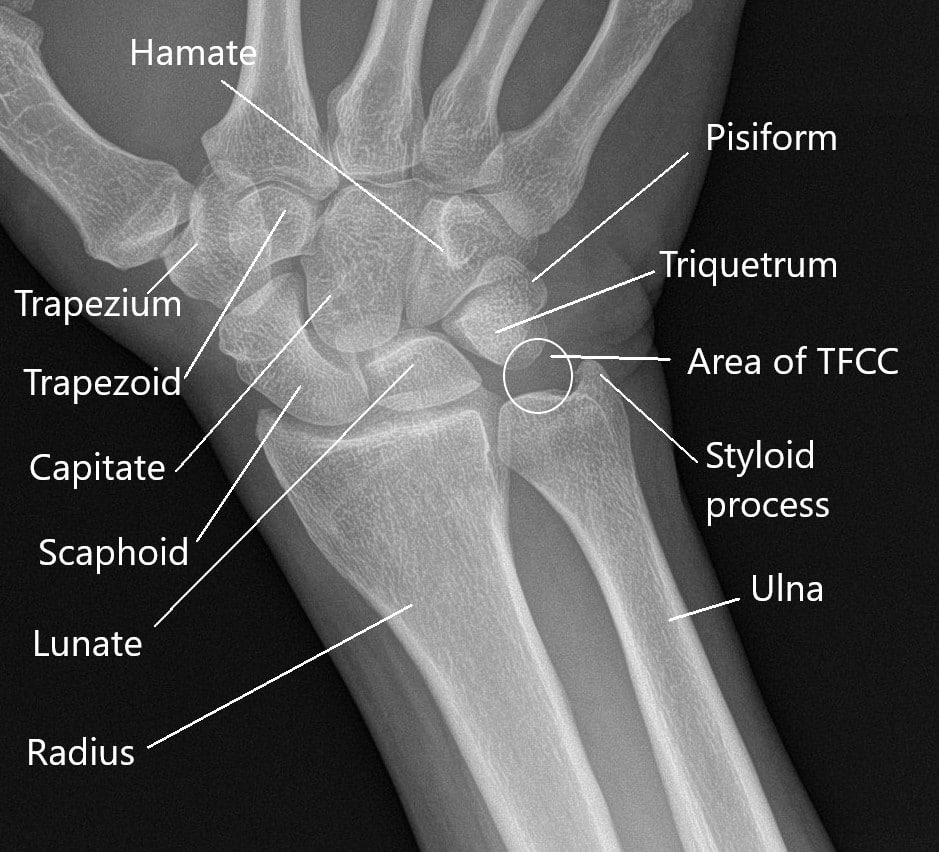

Prepare to be captivated by Top, a showcase of x ray of right hand and wrist imagery powered by wonderkidsmontessori.edu.vn. More related visuals are below.

x ray of right hand and wrist

Posts: x ray of right hand and wrist